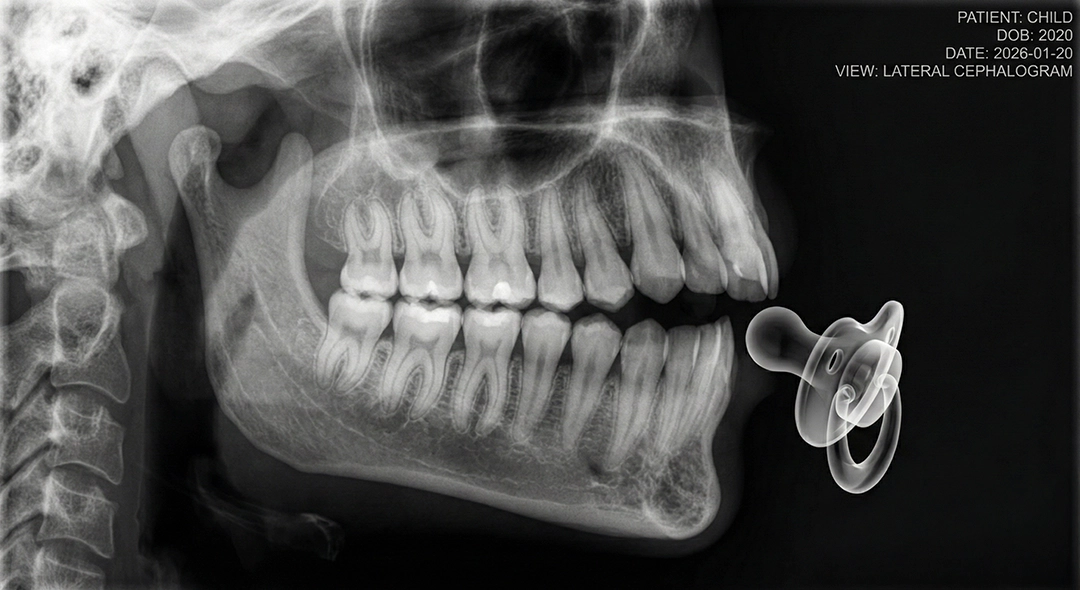

As children grow, however, the habits that once helped them settle can begin to influence how their teeth and jaws develop. A child’s mouth is still forming, and over time, even gentle pressure can shape a growing smile.

A child’s teeth and jaws are in a constant state of growth during infancy and early childhood. The facial bones are soft and adaptable, shaped by everyday functions such as swallowing, speaking, and muscle movement.

When a pacifier remains in the mouth for extended or frequent periods, it can disrupt this natural balance. The tongue may rest lower than normal, while the lips and cheeks exert ongoing pressure in new ways. As teeth begin to emerge, these forces can influence their position and the way the jaws relate to one another.

When pacifier use continues beyond the early years, it is most commonly associated with specific and recognisable bite changes. These occur gradually as the developing teeth and jaws adapt to repeated pressure.

An open bite occurs when the upper and lower front teeth do not touch when the mouth closes, leaving a visible gap even though the back teeth meet. This pattern is strongly associated with prolonged pacifier or thumb habits, particularly when the pacifier is held in the mouth for long periods each day.

Overjet refers to the horizontal distance between the upper and lower front teeth. Extended pacifier use can encourage the upper front teeth to move forward, especially when the tongue rests in a lower position and no longer provides balanced support during growth.

Ongoing pressure from a pacifier can restrict the natural widening of the upper jaw. As a result, there may be limited space for erupting teeth, increasing the likelihood of crowding or crossbites as permanent teeth begin to emerge.

Encouragingly, many of these changes are reversible in young children. When the pacifier habit is reduced or stopped early, often before the age of three, the teeth and jaws can return to a more natural pattern of development without the need for intervention.